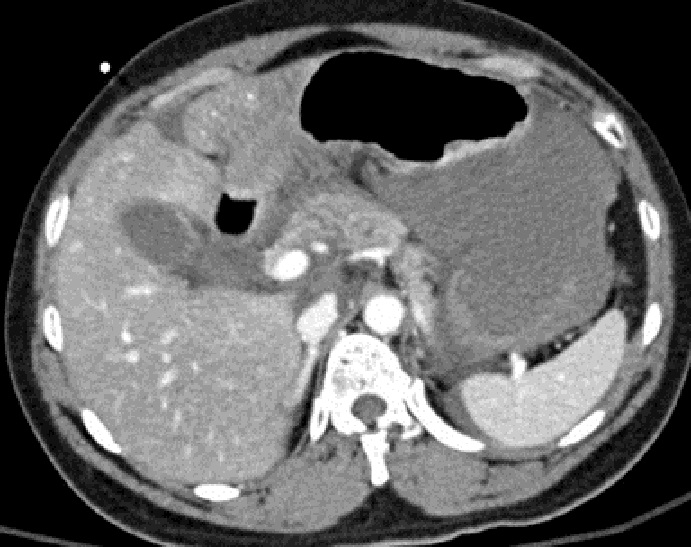

Image radiologique TDM

d'une traumatisne du pancreas avec aspect

lesionnel d'elargi volumineuse heterogene et a

hypodense de la tete du pancreas ( fleche rouge ) .

Coupe axiale TDM non contrast intraveineuse |

Traumatisme de la tete du pancreas avec

hematome hyperdensite legere intra-pancreatique ( fleche )

. La tete et le corps du pancreas est volumineuse a

hypodensite et non homogene Image radiologique TDM en coupe axiale |